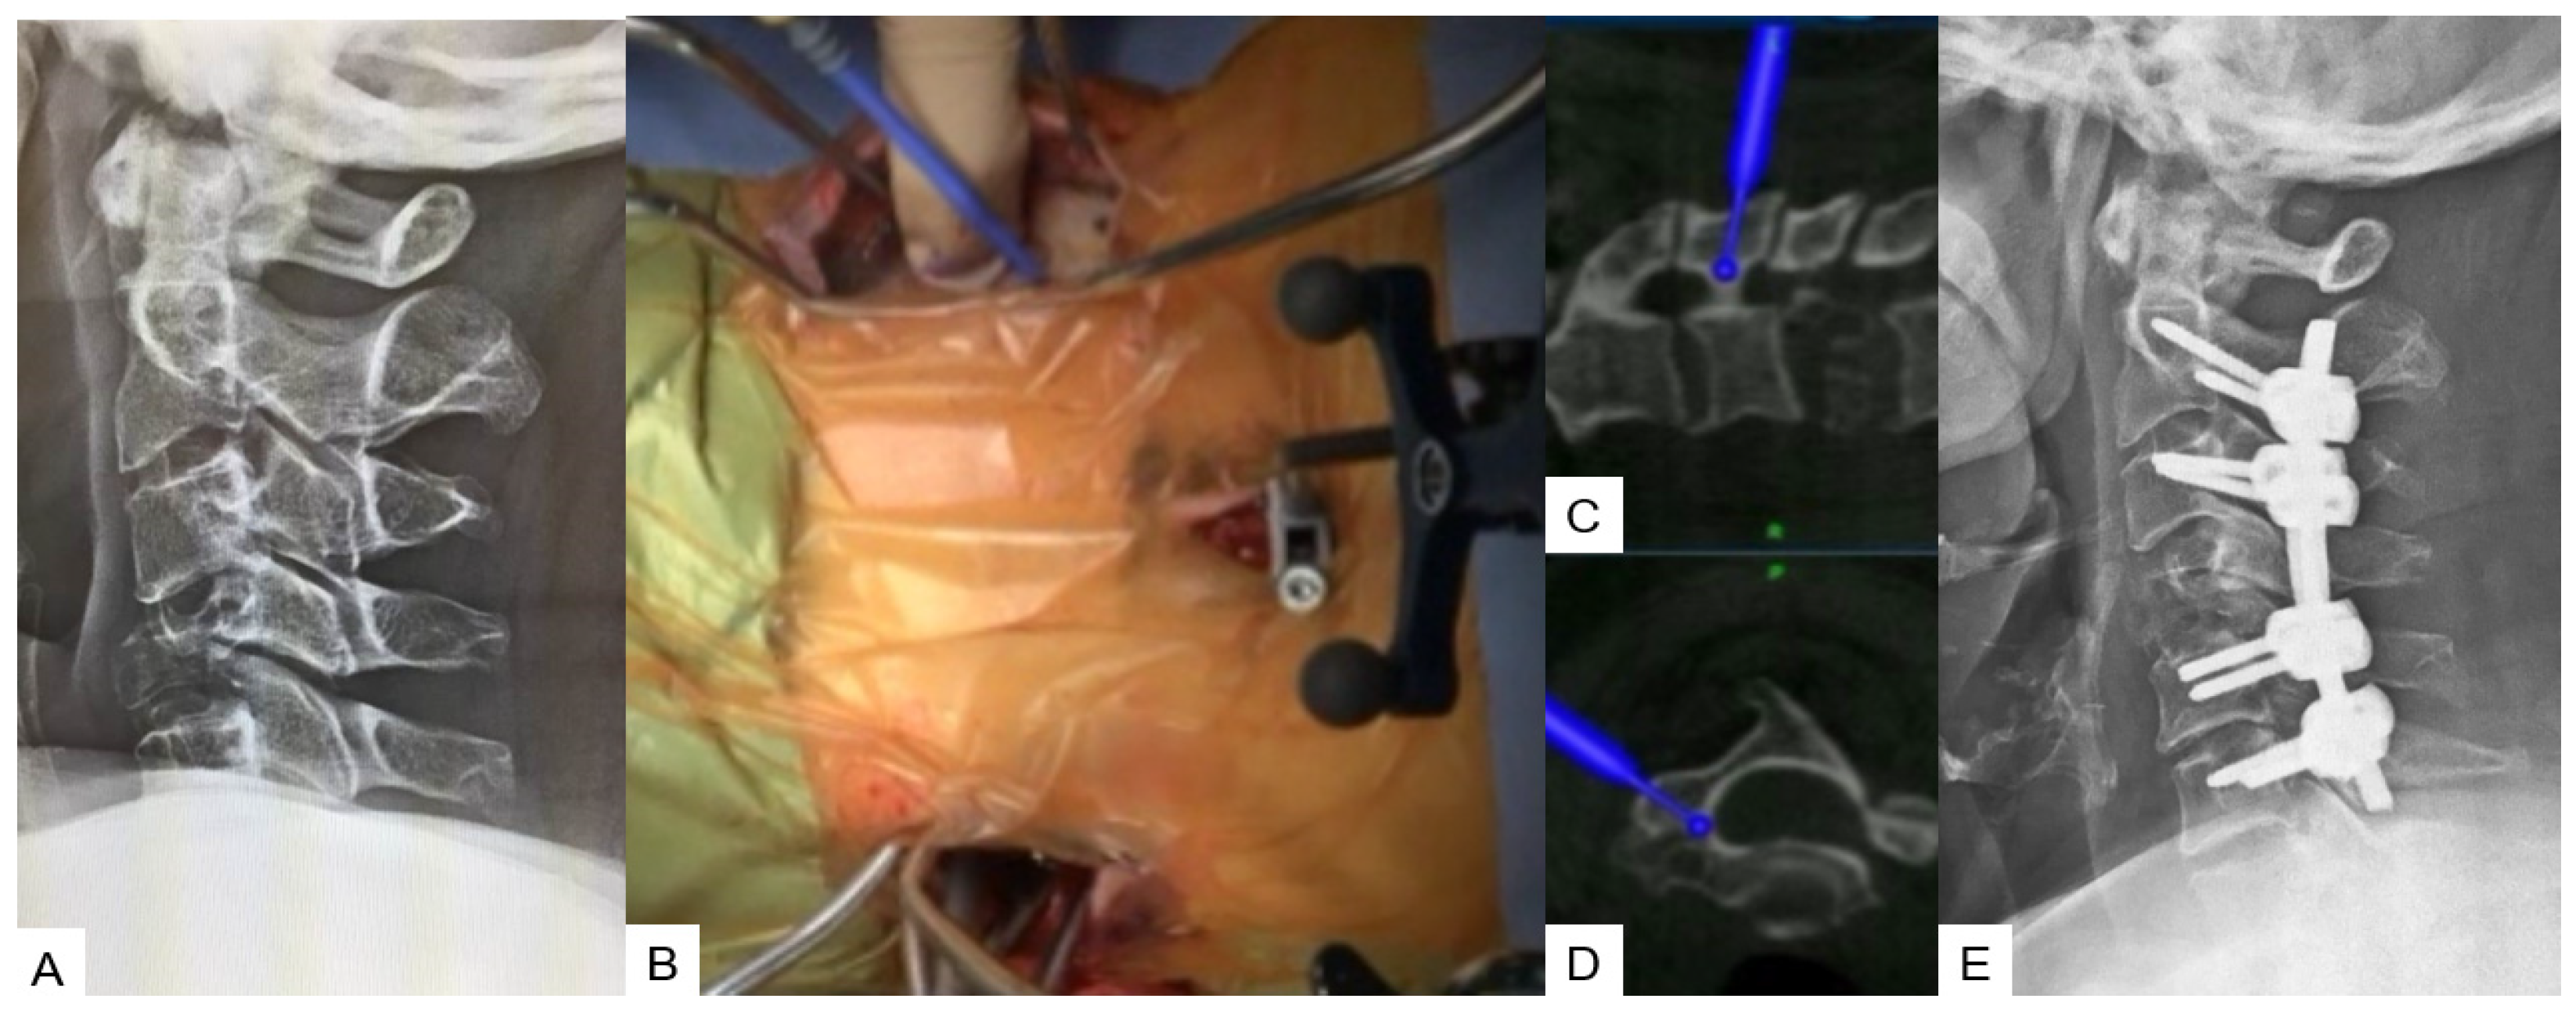

2.2.4. Minimally Invasive Cervical Pedicle Screw Fixation (MICEPS)

- Tanaka, M.; Fujiwara, Y.; Uotani, K.; Kadiri, V.; Yamauchi, T. C-Arm-Free Minimally Invasive Cervical Pedicle Screw Fixation (MICEPS): A Technical Note. Acta Med. Okayama 2020, 74, 551–556. [Google Scholar] [PubMed]